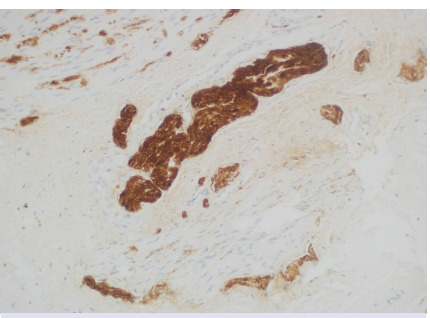

Results: 107 patients were included. There were 66 men (61.6%) and 41 women (38.3%). The median age at biopsy was 15 (1-196) months. FTRB was performed in 81 patients who were unable to pass meconium in the first 48 hours or had intractable constipation. A stoma was performed in 26 patients before the rectal biopsy. Contrast colon radiography was conducted in 61 patients and/or anorectal manometry in 32 patients. Of the biopsies, 74 were full-thickness while 33 were not. Biopsies were repeated in 12 patients. Of the 49 (45%) patients with aganglionic specimens, data about nerve hypertrophy was reported in 37. Among these, 33 had nerve hypertrophy and 4 did not. A definitive surgery was performed in 44 of the 49 patients diagnosed with Hirschsprung disease (HD). Complications were observed in 7 (6.5%) of the patients.

Conclusion: HD was histopathologically diagnosed. Biopsies that are not full-thickness can be of value when using immunohistochemistry stains.